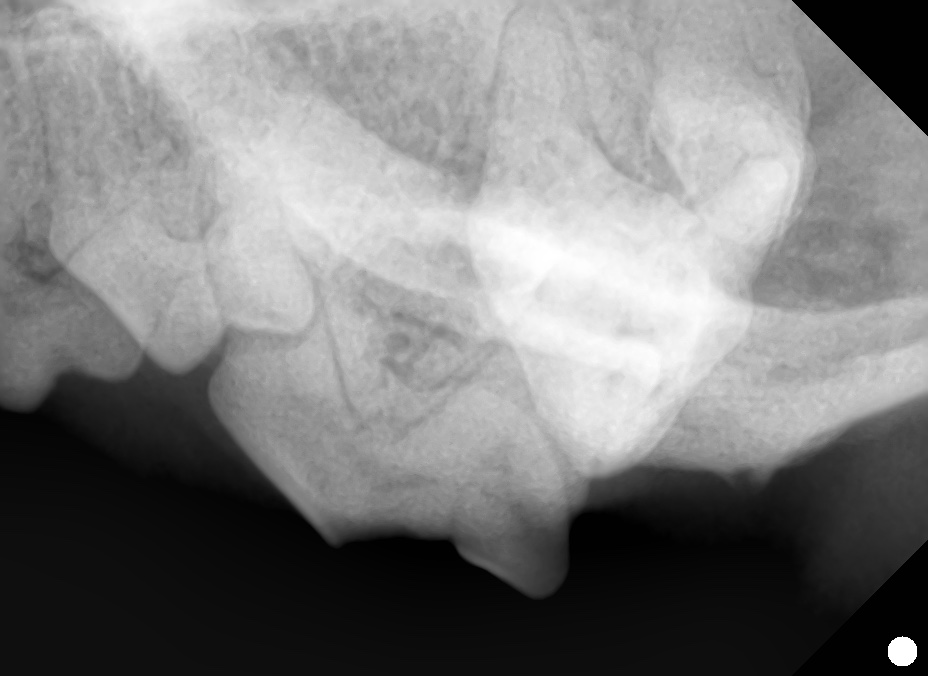

下の写真は第四前臼歯が折れてしまったわんちゃんです。

肉眼的には露髄しているかどうか判断が難しく、歯科レントゲンの撮影を行いました。

破折部位には象牙質が残っており、歯髄腔にギリギリ達していないと判断しました。

象牙質は再生するため露髄してから再生した可能性も否めませんが、根尖周囲病巣がないことを確認し神経を温存する治療を選択しました。